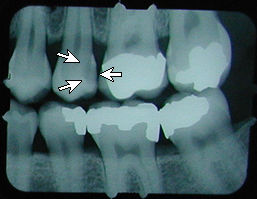

No cavity on first X-ray.

|

Months later, cavities that start

between the teeth can't be seen by visual examination,

but they can be detected on an X-ray.

|

This cavity was detected and filled before the patient felt any discomfort, and before the nerve became infected or the tooth became abscessed.

There is another cavity shown in the X-ray on the right. Can you find it? It's difficult for the untrained eye to spot. Click here to see where it is. (Hint: It's not the left edge of the top left tooth. That's just the edge of the frame around the X-ray).